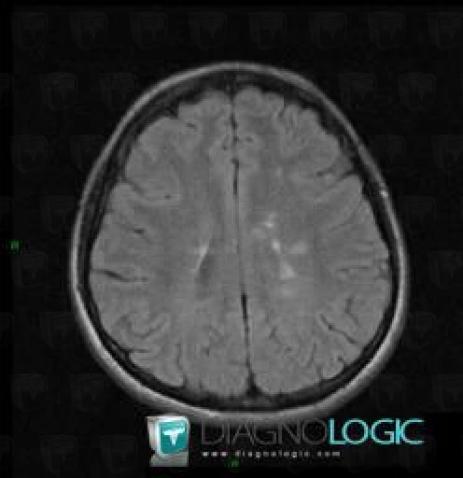

Multiple sclerosis, Cerebral hemispheres, MRI

Here is the specific information in the key image above:

- Diagnosis Multiple sclerosis, Location(s) Cerebral hemispheres, with gamuts Intracerebral lesion with moderate enhancement